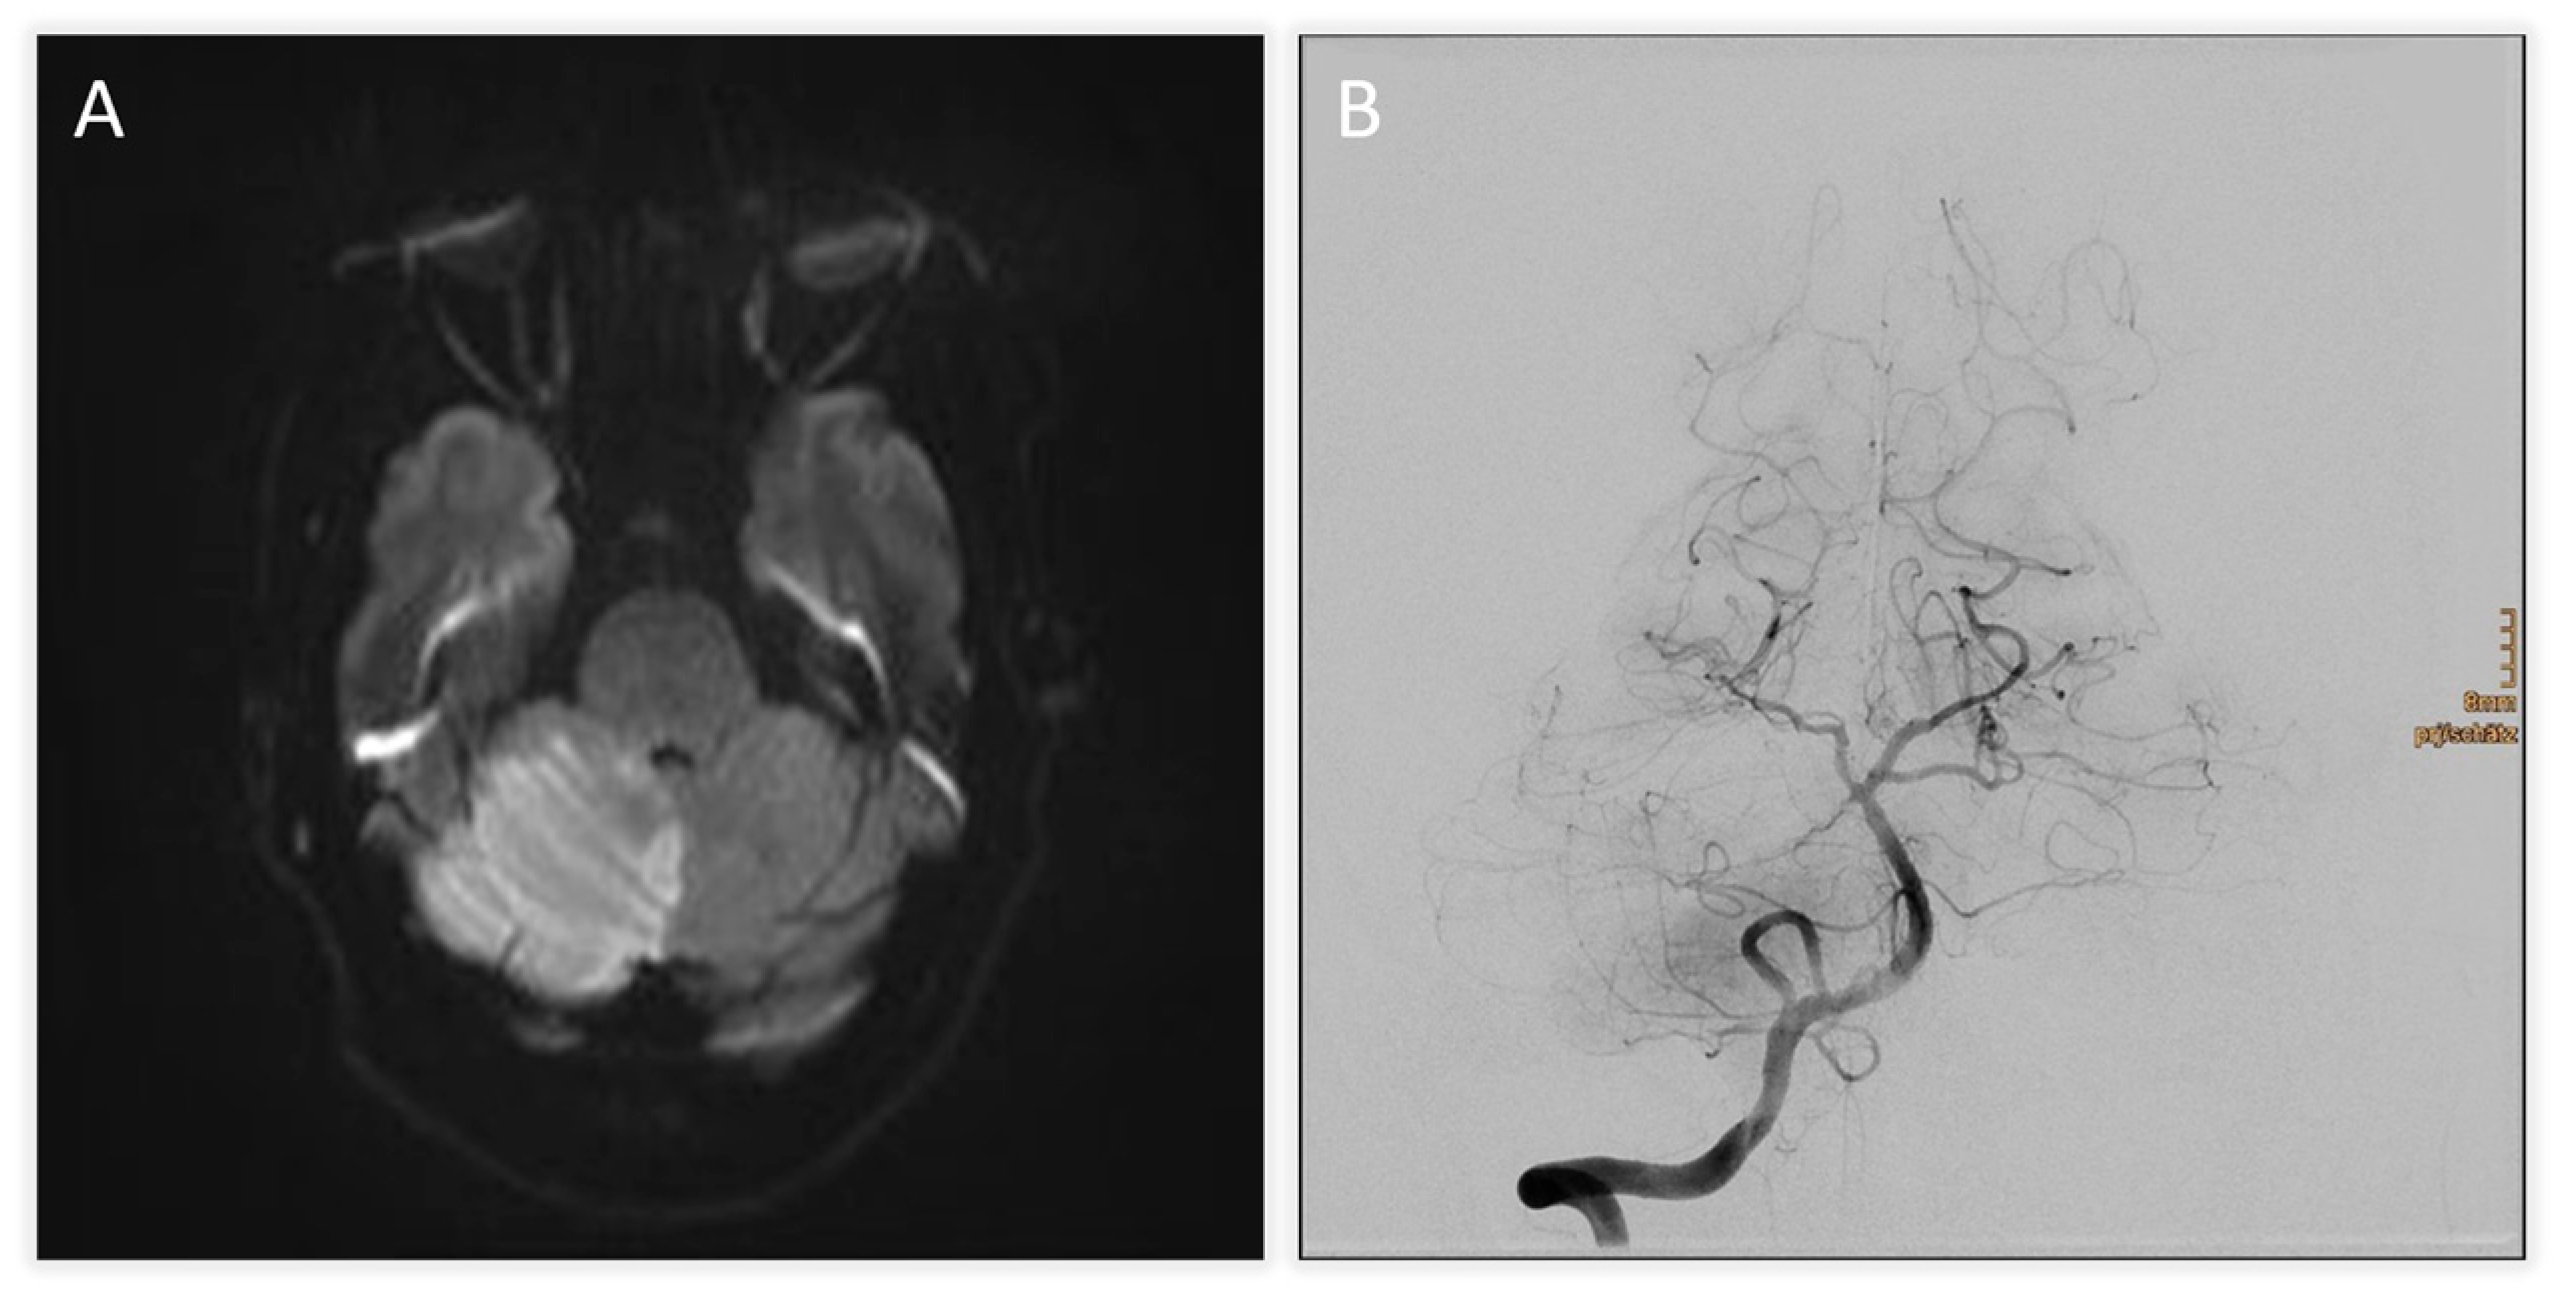

| +2 h (admission) | Initial MRI (DWI) + TOF-angiography | Acute infarction of right cerebellum and vermis; thrombus at basilar tip; right SCA occlusion |

| +4 h | Digital subtraction angiography (DSA) | Basilar tip patent, right SCA occluded; mechanical thrombectomy attempted but unsuccessful |

| +6 h | CT scan | Expanding right cerebellar infarct with mass effect; apparent hypodensity in pons, midbrain, diencephalon → suspicious for brainstem infarction |

| +7 h | MRI follow-up | Brainstem infarction excluded; predominant cerebellar edema confirmed |